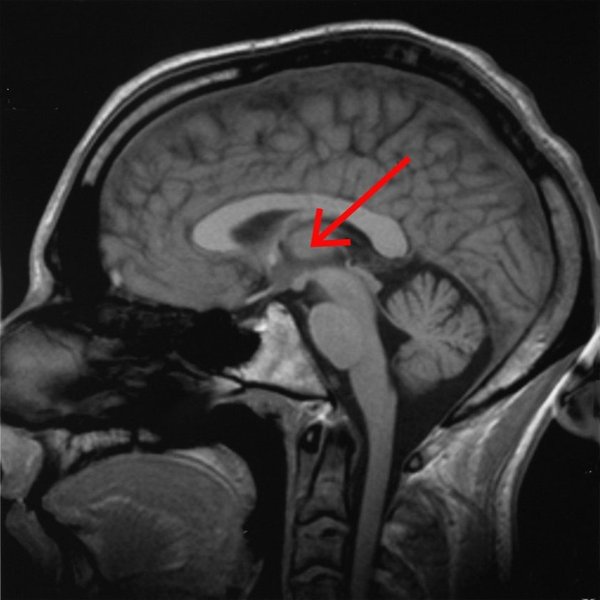

Так, команда ученых выяснила, что при частоте 50 Гц электрическая стимуляция центрального бокового таламуса позволила выводить подопытных обезьян из-под анестезии и демонстрировать нормальное бодрствующее поведения. Стоит подчеркнуть, что таламус отвечает за передачу информации от органов чувств и играет важную роль в регуляции уровня сознания, процессов сна и бодрствования, концентрации внимания.

Отдел головного мозга таламуса. Фото: AxelBoldt/Wikimedia Commons